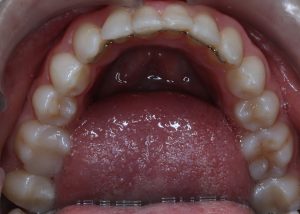

Maloclusión

Se caracteriza por una alineación incorrecta de los dientes, donde los dientes superiores e inferiores están en una relación normal, pero hay una falta de espacio que provoca que los dientes se solapen o estén apiñados.

Este problema puede generar dificultad para mantener una correcta higiene dental y afectar la estética de la sonrisa

INITIAL

22 Semanas de Tratamiento